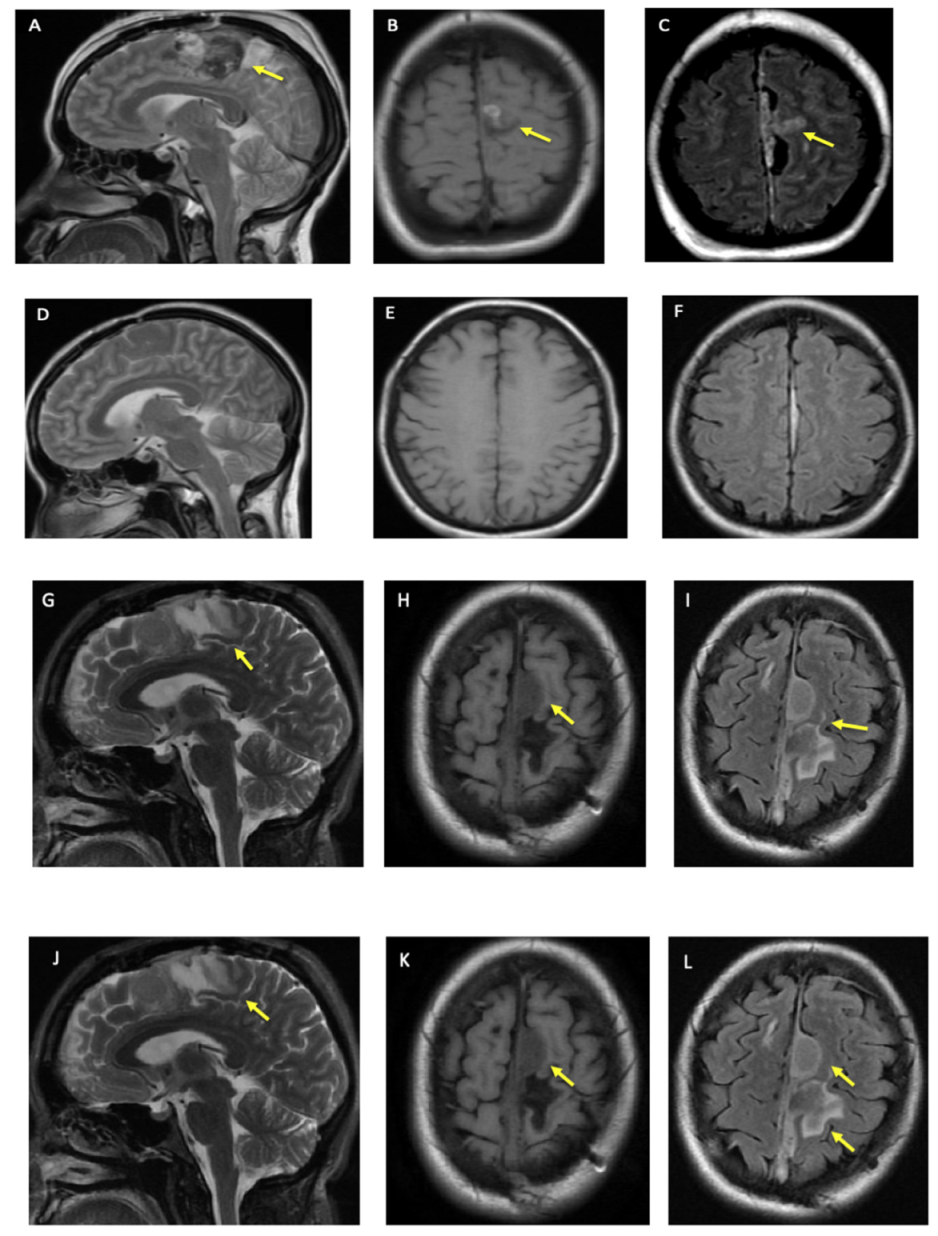

A woman in her 40s with hypertension and diabetes mellitus presented with acute onset of right foot drop and headache (HA) in 2013 that she described as the “worst headache of her life”. Her physical exam was significant for moderate to severe weakness of the right lower limb. A CT scan of the head showed a 2 cm subdural hematoma at the left anterior falx with a regional mass effect. Intraoperatively, a mass at the falx was found and was biopsied. Postoperative magnetic resonance imaging (MRI) showed “left parafalcine enhancing thickening,” which was followed by serial MRIs (Figure 1A–F).

Figure 1.

Patient’s Brain MRI. (A–C) show brain MRI at the time of initial presentation in 2013, (A) is T2, (B) is T1 FLAIR, and (C) is T2 FLAIR. (D–F) is brain MRI 3 months after the patient’s initial craniotomy. (D) is T2, (E) is T1 FLAIR, and (F) is T2 FLAIR. (G–I) is 7 years after initial MRI, (after the patient was on cobimetinib for 6 months). (G) is T2, (H) is T1 FLAIR, and (I) is T2 FLAIR. (J–L) are 8 years after initial MRI, (on cobimetinib for 13 months). (J) is T2, (K) is T1 FLAIR and (L) is T2 FLAIR. Single yellow arrows in different figures shows the lesion after biopsy and debulking. In (L), anterior and first arrow is highlighting meningioma in addition to lesion as denoted by 2nd and posterior arrow.

In 2020, the patient started cobimetinib, and has not had any progression in clinical and imaging findings (Figure 1G–L). In addition, there are no clinical or radiographic findings to suggest other system involvement over the last eight years.